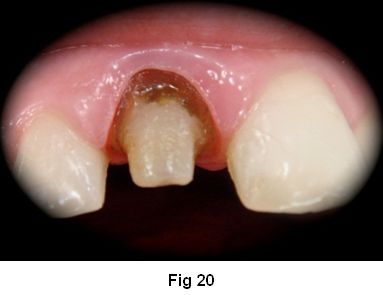

Tecnica Del Poste Anatomico Grandini Caso Clinico

www.scielo.edu.uy